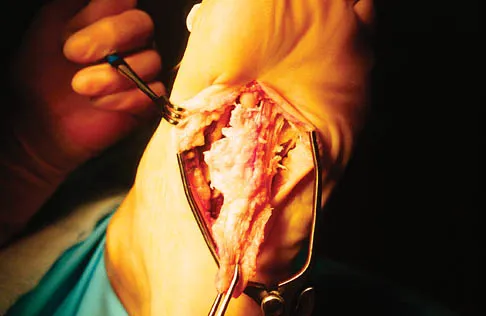

Question 56

A 56-year-old woman has a painful mass on the bottom of her left foot, and orthotic management has failed to provide relief. Examination reveals that the mass is contiguous with the plantar fascia. An MRI scan shows a homogenous nodule within the plantar fascia. Resection of the tumor is shown in the clinical photograph in Figure 39. What type of cell is most likely responsible for the formation of this tumor?

Explanation